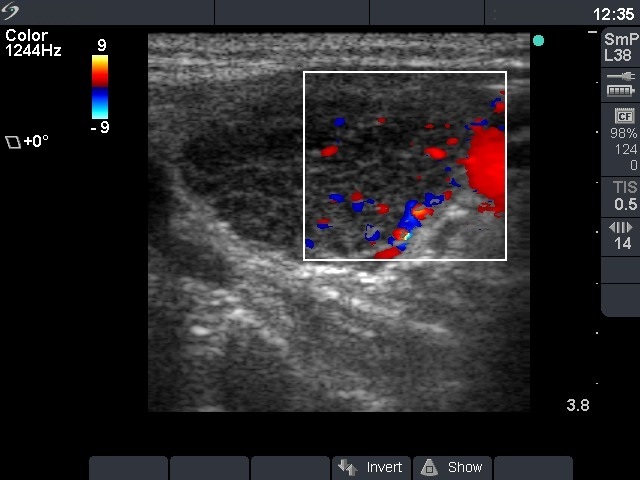

Ultrasonography: the thyroid was minimally hypoechogenic. There were small hypoechogenic areas in the right, while a large nodule-like hypoechogenic lesion with extensive fibrotic changes in the left lobe. The surface of this lesion was irregular. Type 3 vascular pattern was detected, i.e. there was no perinodular blood flow. We could not exclude the possibility that this lesion was a nodule, but the whole pattern was consistent with autoimmune thyroiditis.